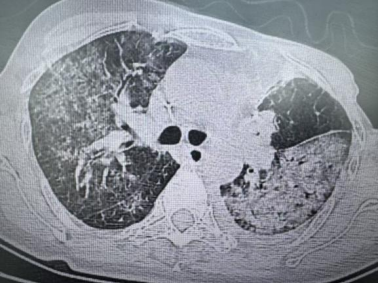

我院肺病科团队接诊后,第一时间启动免疫低下人群肺部感染急症诊疗流程。结合化疗后骨髓抑制病史,高度怀疑 PJP,快速完善外周血淋巴亚群分析、G试验等检查,胸部 CT 见双肺弥漫性磨玻璃样影,符合 PJP 典型影像学特征。团队争分夺秒为患者行气管镜肺泡灌洗,灌洗液送检 t-NGS(病原靶向高通量测序),同时给予氧疗、对症支持等治疗,维持患者呼吸循环稳定。24 小时内 t-NGS 检出耶氏肺孢子菌,结合各项检查确诊 PJP,随即予复方新诺明靶向抗真菌治疗,辅以保肝护胃及中医扶正调理。经规范治疗半月后,患者干咳、气促症状完全缓解,血氧饱和度恢复至正常水平,复查胸部 CT 提示双肺弥漫性病灶显著吸收,现已顺利出院,回归正常生活。这一病例的成功救治,得益于我院肺病科对免疫低下人群肺部感染的快速识别能力、完善的急症诊疗流程,以及气管镜肺泡灌洗 + t-NGS 的精准检测技术,为抢救赢得了宝贵时间。